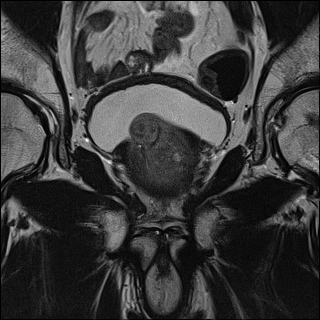

Refer to caption

(a) Ground Truth

(b) Low resolution input

(c) Proposed SR Result

Figure 1: Example of Data and Proposed Result

We first convert the DICOM format of the input images to PNG to make them compatible with our models and resize the images so that the random cropping function, which produces 224×224224224224\times 224 crops, works correctly. We additionally scale the images so that the pixel values range from -1 to 1. An example of the data and proposed SR solution is shown in Fig. 1. We run all of the ML SR techniques on Google Cloud using an NVIDIA Tesla K80 GPU to accelerate training.